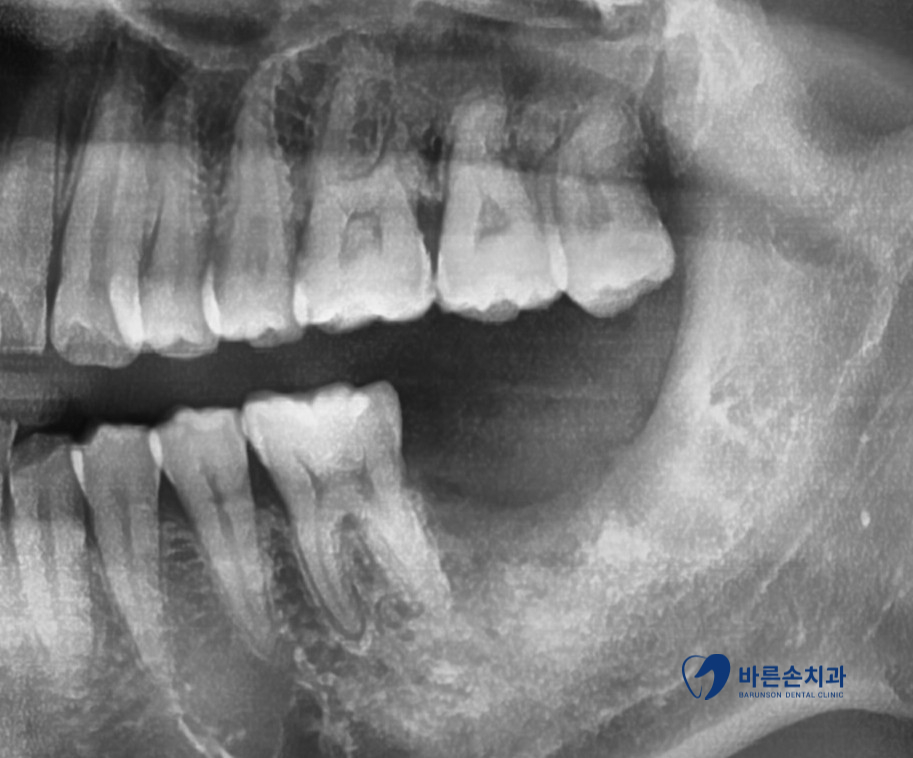

환자분 같은 경우에는

워낙 충치의 범위가 넓고 남아있는 치아의 양이 적어 살릴 수 있는 방법이 없어

아쉽지만 사랑니와 함께 발치를 해드렸습니다.

사랑니는 따로 임플란트를 할 필요는 없지만!

사랑니와 같이 빼게 된 앞 치아는 씹는데 중요한 역할을 하는 치아이기 때문에

추후 임플란트 치료하여 꼭! 수복을 해주셔야 합니다.